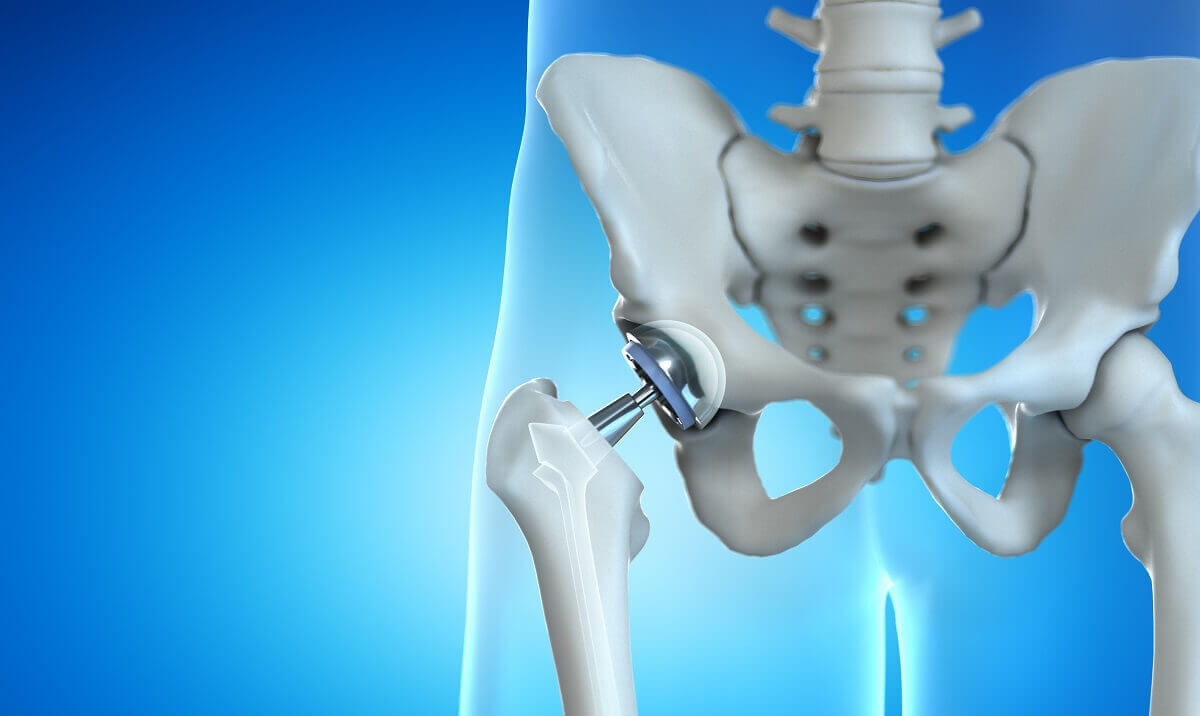

Η αρθροπλαστική ισχίου, γνωστή και ως χειρουργική επέμβαση αντικατάστασης ισχίου, είναι μια χειρουργική επέμβαση κατά την οποία μια κατεστραμμένη ή άρρωστη άρθρωση του ισχίου αντικαθίσταται με μια τεχνητή άρθρωση, που ονομάζεται πρόσθεση. Η πρόθεση έχει σχεδιαστεί για να μιμείται τη φυσική κίνηση της άρθρωσης του ισχίου, επιτρέποντας βελτιωμένη κινητικότητα και μειωμένο πόνο.

Η χειρουργική επέμβαση περιλαμβάνει την αφαίρεση των κατεστραμμένων ή άρρωστων τμημάτων της άρθρωσης του ισχίου και την αντικατάστασή τους με μια πρόσθεση από μέταλλο, πλαστικό ή κεραμικό.

Υπάρχουν δύο κύριοι τύποι αρθροπλαστικής ισχίου: η ολική αρθροπλαστική ισχίου, στην οποία αντικαθίσταται τόσο η μπάλα όσο και η υποδοχή της άρθρωσης του ισχίου και η μερική αρθροπλαστική ισχίου, στην οποία αντικαθίσταται μόνο η μπάλα ή η υποδοχή.